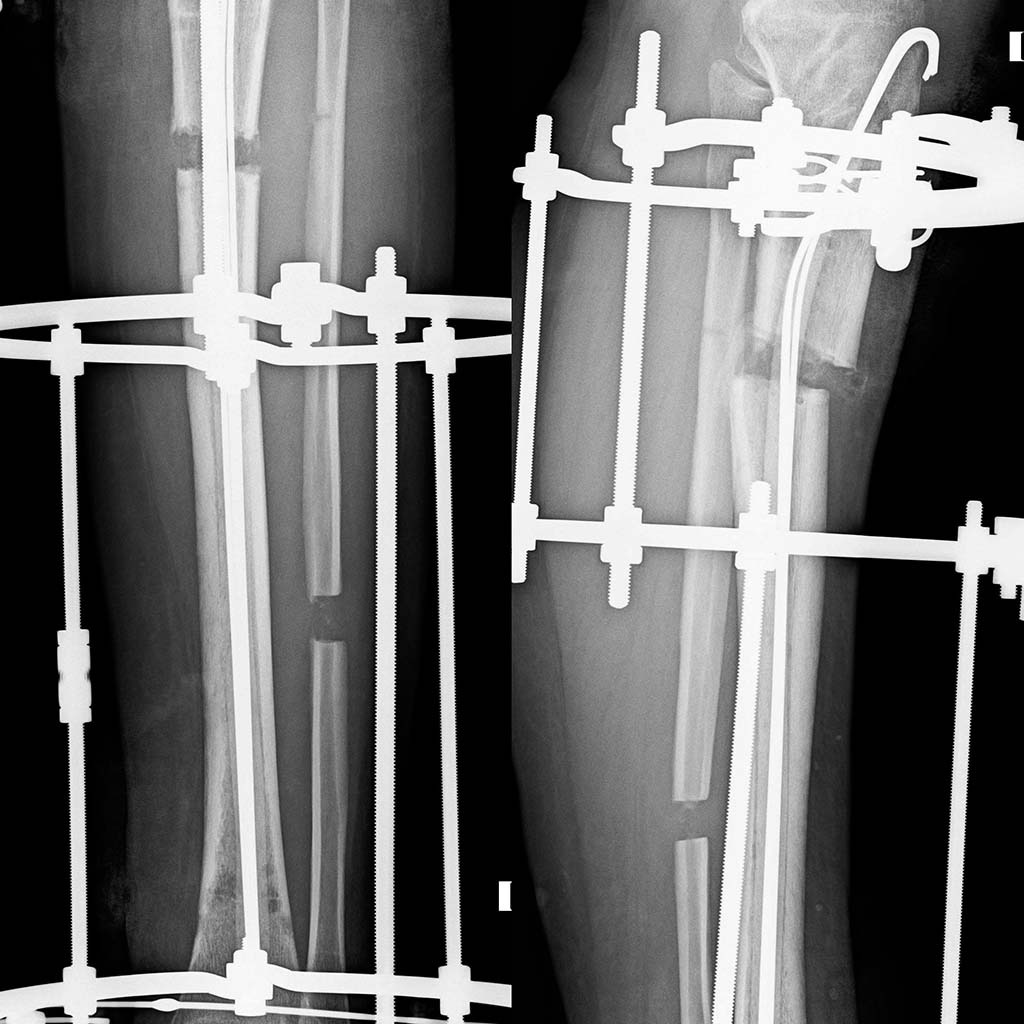

Из собственного опыта. Не надо тешить себя надеждой, что воспалительный процесс только в мягких тканях вокруг блокирующих винтов. Инфекция в костномозговом канале. Косвенное подтверждение – нагноение сразу всех дистальных блокирующих винтов, которые проведены полифокально. Стержень необходимо удалять.

Боюсь, тут полумеры могут не решить проблему. Наверно, стоило бы наложить аппаратик, убрать гвоздь, ввести на всю длину гвоздя спейсер из цемента с антибиотиком. Через пару недель, после купирования всех проявлений, заново заштифтовать. Наверно, сделать гвоздь с покрытием. Ну и дистальные винты взять правильной длины, сейчас коротковаты.

Попутно исправить недоточеты вверху. то есть ввести отклоняющие спицы, чтобы устранить вальгус и переднезаднее смещение.